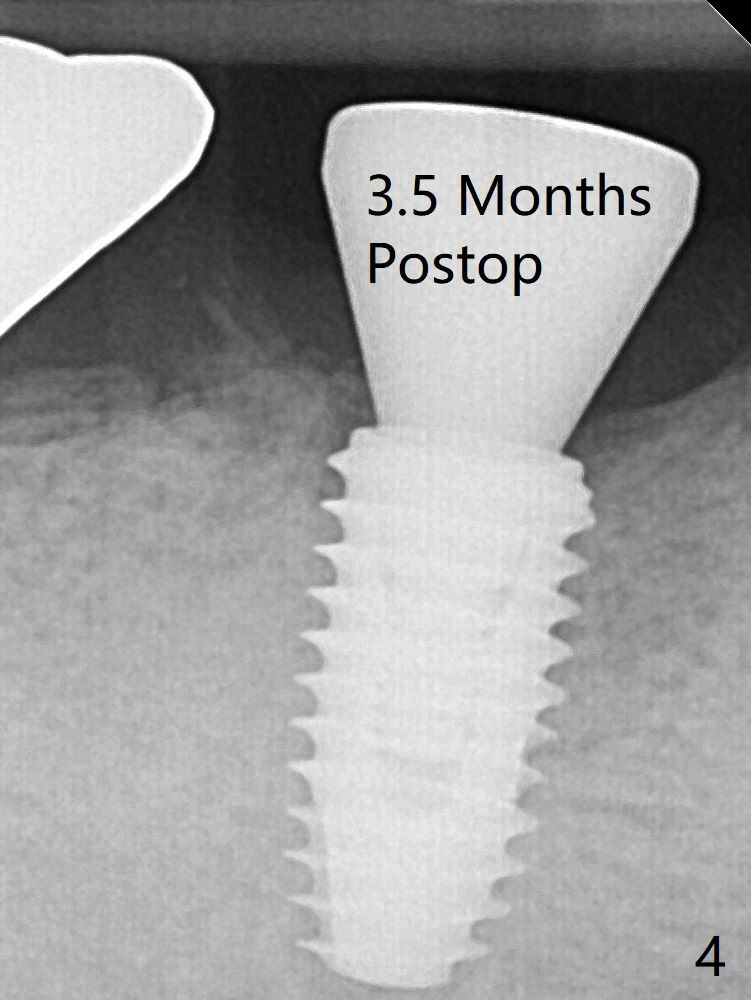

To reduce heat-induced bone necrosis at #19, osteotomy is conducted slowly with copious irrigation with cold saline. Bone density is felt while a 5x10 mm implant is being placed after using cortical tap to the 2nd line of the implant driver. The implant needs to be reverse torqued several times before reaching its final depth (Fig.1 (~50 Ncm)). Since the residual roots are superficially positioned, the immediate implant looks as a delayed one. Although the implant is placed mesial to the septum clinically, its position in X-ray seems to be normal. Because of severe wear and lack of vertical height, a 6.8x5 mm healing abutment is placed. Retention of bone graft placed in the distal socket (Fig.1 *) is maintained by spreading setting acrylic into the edentulous undercut areas. The bone graft placed in the distal socket appears to have been converted to the native bone 3.5 months and 4 months postop (Fig.4,6).